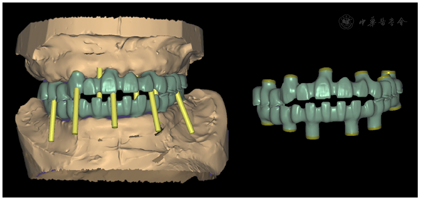

治疗过程:(1)术前准备:①藻酸盐取初印模,制作个性化托盘(图4);②用个性化托盘取硅橡胶终印模,灌制终模型;③制作光固化树脂

托及蜡堤(图5),面部比例二等分法确定垂直距离,肌肉疲劳法及吞咽咬合法确定水平关系,面弓转移患者颌位关系,上

架;④排牙,制作放射导板(图6A);⑤试戴放射导板(图6B~D),拍摄两次CBCT(患者佩戴放射导板拍摄CBCT以及放射导板单独拍摄CBCT)。(2)方案设计:①将两次CBCT获取的DICOM数据导入种植设计软件重叠(图7),以修复为导向指导上下颌种植体位置摆放(图8、图9);②生成并打印手术导板(图10)。(3)利用手术导板和导板锁,翻制模型,制作临时修复体(图11)。(4)一期手术过程:铺巾消毒,局麻后拔除上下颌余留牙,搔刮拔牙窝内炎性肉芽组织,于34-36、44-46区牙槽嵴顶近远中向切开牙龈,翻瓣。就位并固定手术导板,于11、13、16、22、25、26、32、34、36、42、44、46定点,按术前设计方案植入NobelParallelTM ConicalConnection种植体。除26区种植体外,其余种植体初期稳定性均达到35N.cm以上,就位复合基台,戴入保护帽,修整牙龈黏膜,缝合牙龈(图12A~F)。术后拍摄全景片(图13)。次日复诊,取下保护帽,戴入预制的临时修复体,调合(图12G)。

治疗结果:术后3个月全景片显示种植体骨结合良好(图14)。26牙行二期手术,就位复合基台,戴入保护帽。两周后,取下临时修复体,制取上下颌硅橡胶印模,利用临时修复体交叉上

架转移患者颌位关系。设计数字化桥架(图15),切削铝制支架。试戴铝制支架,拍摄全景片显示支架被动就位良好(图16)。按照铝制支架切削纯钛支架,上聚合瓷,患者右侧咬合空间不足,设计金属